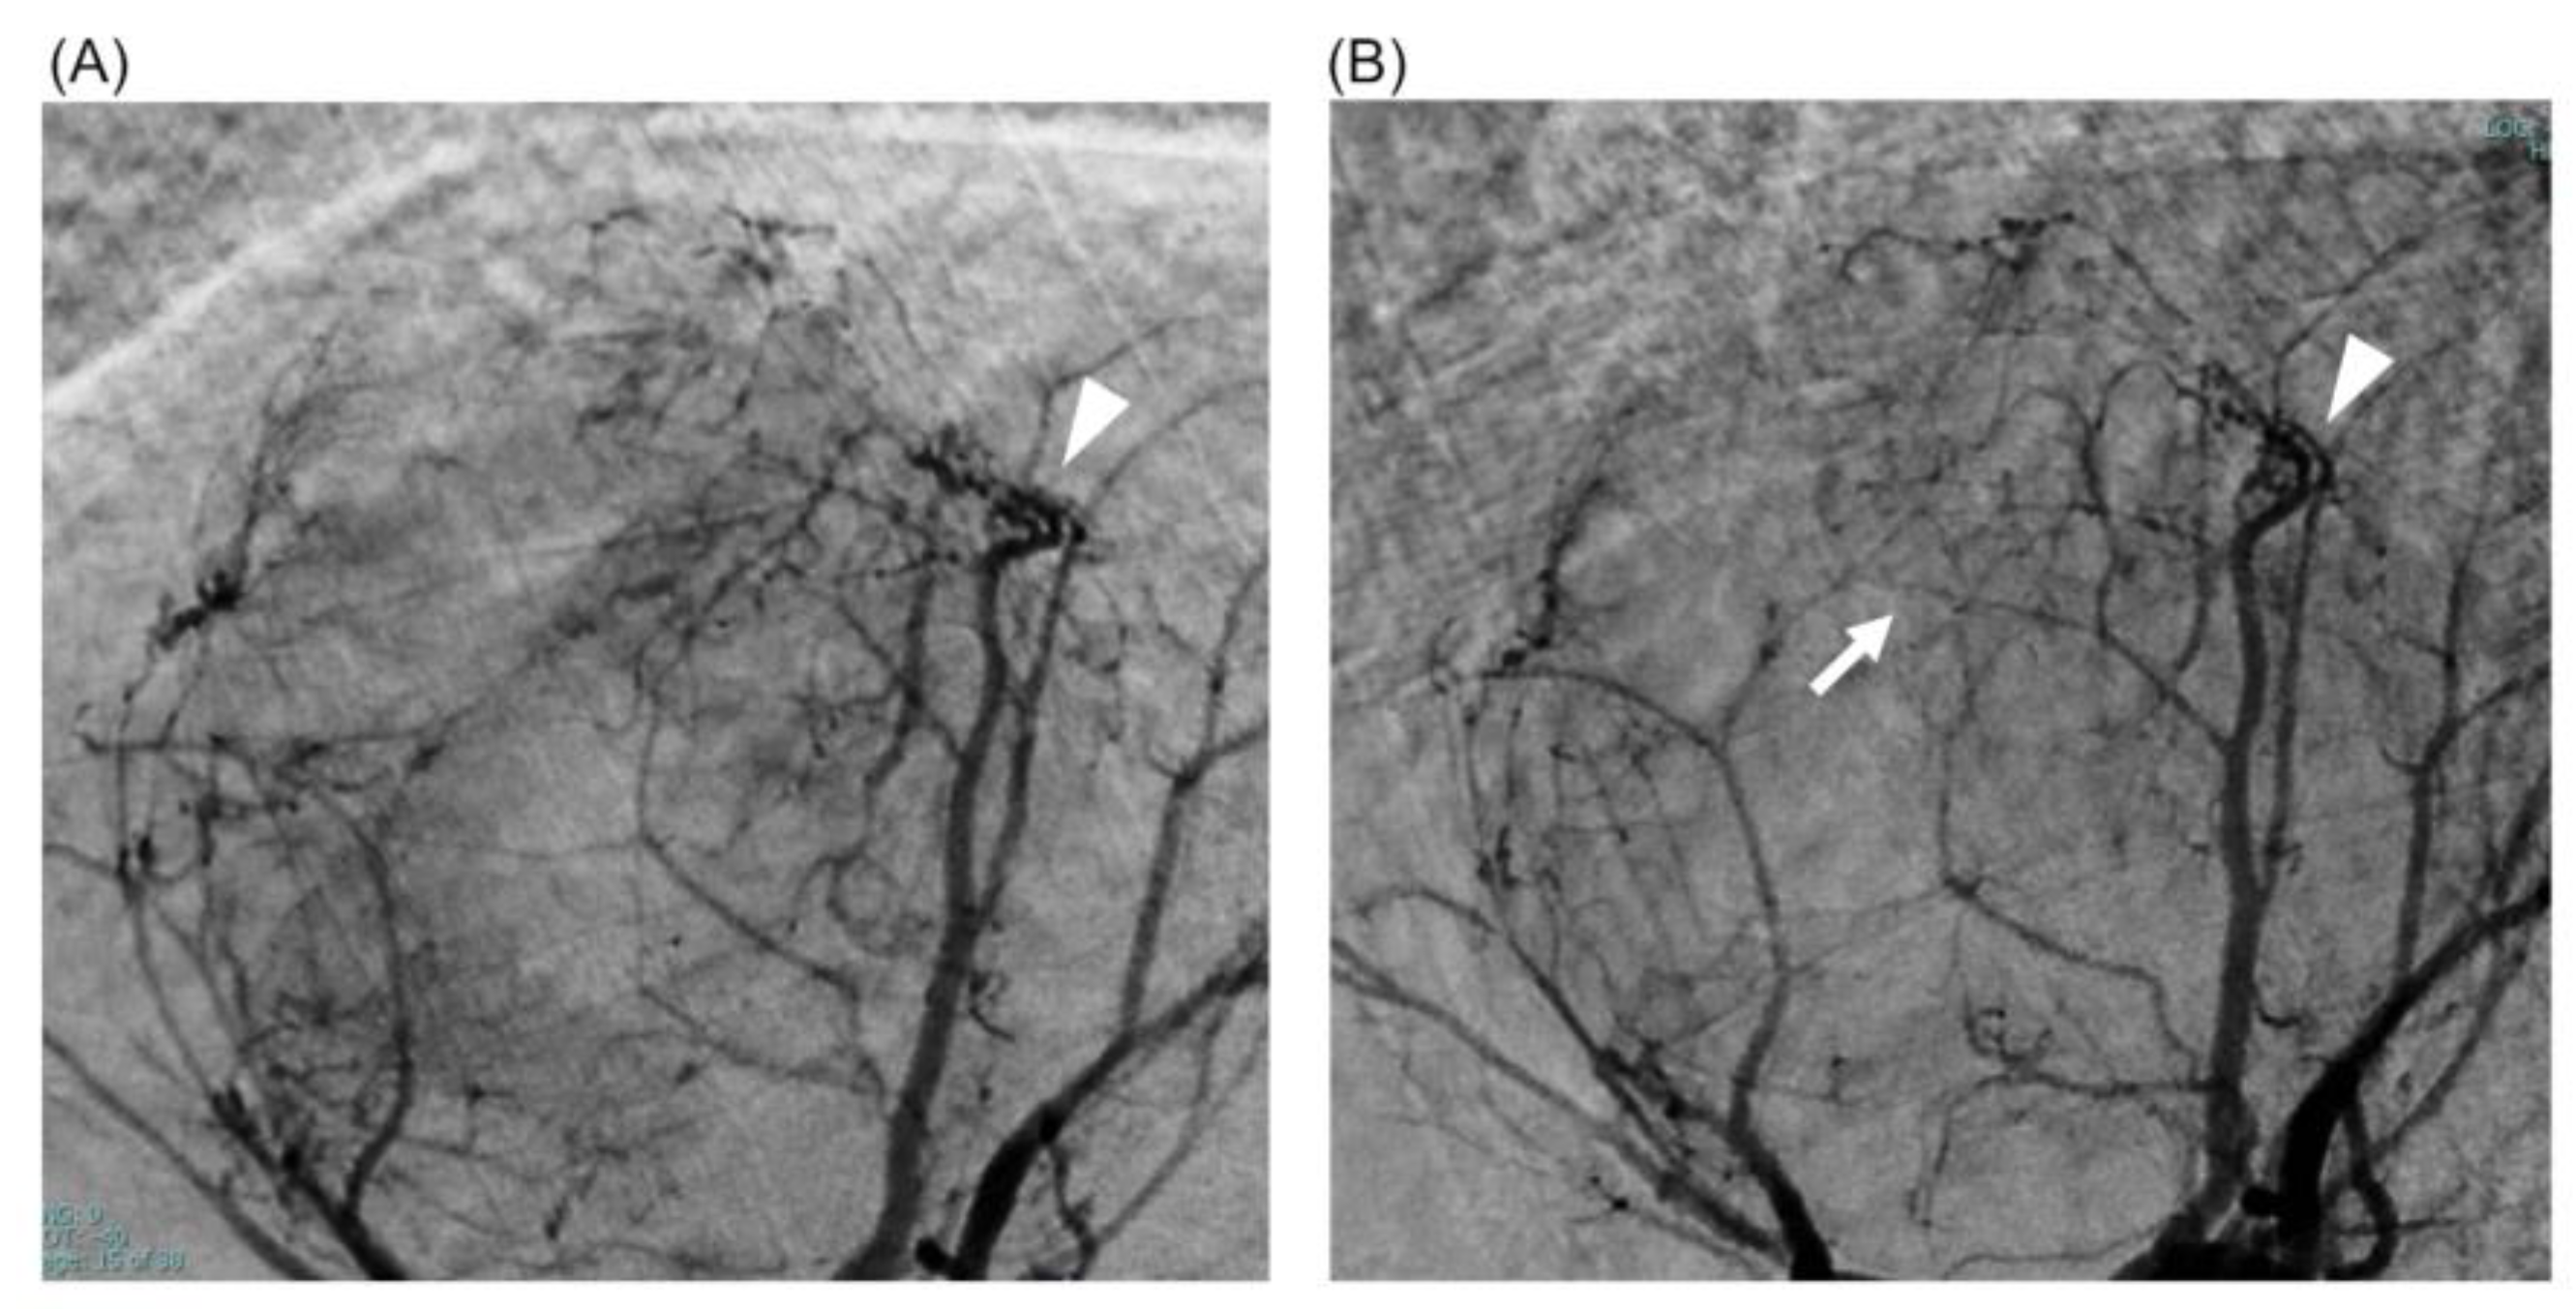

2.1. Case 1

2.2. Case 2